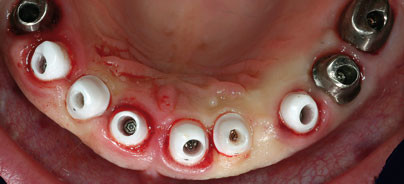

Im Rahmen der Operation erfolgte nun zunächst die ­lasergestützte Parodontalbehandlung mithilfe des Photolase®-Verfahrens (Abb. 4a). Die anschließende Zahnentfernung im Bereich der Maxilla wurde gefolgt von einer Konditionierung des zervikalen Epitheliums unter Einsatz des Erbium-Chromium-YSGG-Lasers (Millennium Waterlase, Firma Biolase; Abb. 4d). Danach wurde die NobelGuide™ Schablone intraoral fixiert. Die Lagefixierung der NobelGuide™ Schablone erfolgte mit vier Ankerpins (Anchorpins, Fa. Nobel Biocare) von palatinal bzw. vestibulär. Auf der rechten Seite wurde ein Sinuslift durchgeführt (Abb. 4c). Bei Benutzung der NobelGuide™ Schablone wurden zehn Implantate in den Kiefer inseriert (Abb. 4b). Die folgenden Implantatgrößen  wurden  eingesetzt: RP 4,3 x 13 mm in der Region 011, 022, 023, 014; NP 3,5 x 13 mm in Region 012, 022; RP 5,0 x 13 mm in Region 015, 024 und 025. Insgesamt wurden Festsetzungsdrehmomente zwischen 45 und 65Ncm erreicht. Die Sofort­belastung der Implantate erfolgte nach individueller Implantatabformung mittels präfabrizierter Perio­Bridge. Als Verbindungsstücke wurden konfektionierte Narrow Profile Abutments (RP und NP 9 mm) verwendet (Abb. 4d).

Unmittelbar nach Implantatinsertion erfolgte die Abformung (Abb. 5) mit herkömmlichen Abformpfosten als geschlossene Abformung. Danach wurden Narrow Profile Abutments eingegliedert und diese mittels Perio­Bridge sofortbelastet (Abb. 6a und b). Die finale pro­thetische Versorgung wurde mithilfe von sechs NobelProcera™ Brücken auf NobelProcera™ Abutments in den Regionen 013 bis 023 etwa drei Wochen durchgeführt (Abb. 7a bis d). Die noch nicht versorgten Implantate 014, 015 sowie 024 und 025 wurden mit NobelProcera™ Brücken verblockt und mit einer distalen Extension versorgt. Als Abutment im Molarenbereich wurde Titan verwendet (Abb. 8a bis d). Die komplette Suprakonstruktion wurde aus Vollkeramik hergestellt.